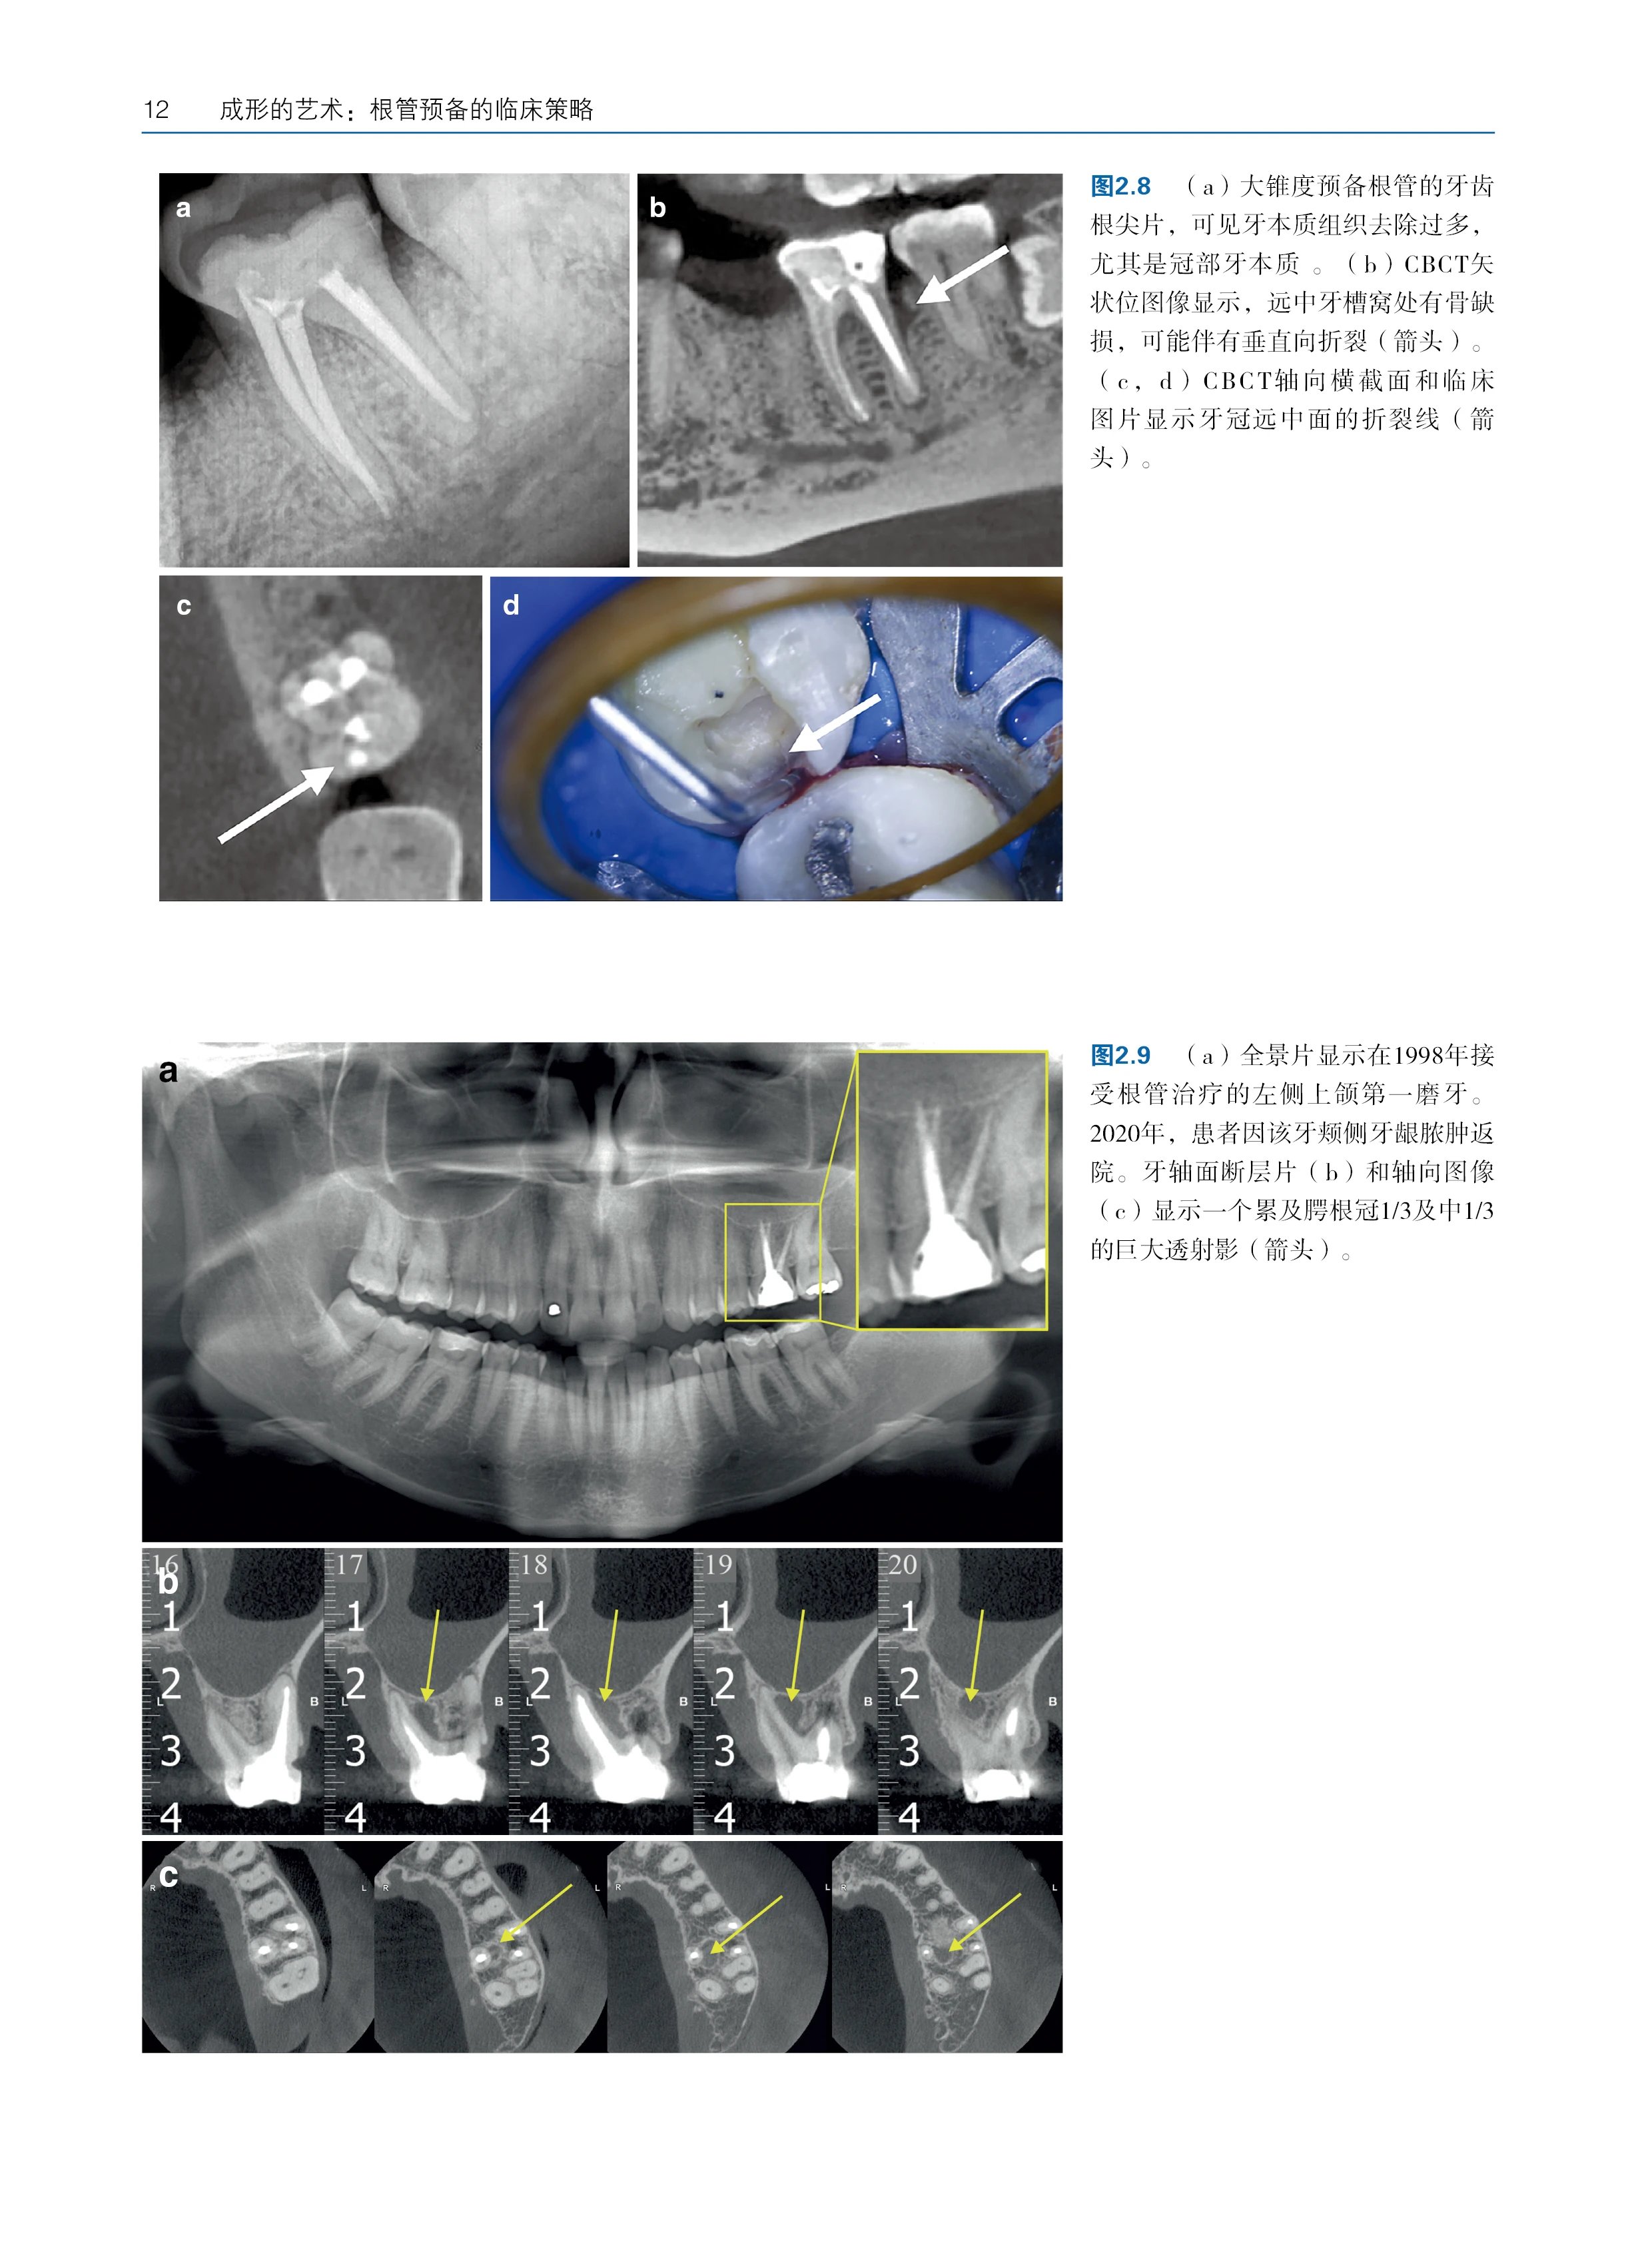

编辑推荐 * 聚焦核心,阐释辩证关系:本书由国际权威专家团队联合编写,系统深入地解析了根管治疗中“清理”和“成形”这对核心概念的辩证统一关系,针对临床医生普遍面临的"过度预备损伤牙体组织"与"残留感染导致治疗失败"的两难困境,指导医生在彻底清除感染与最大限度保存牙体组织之间找到科学精准的平衡点,实现治疗效果与牙齿长期保存的双赢。 * 循证为基,涵盖前沿技术:本书内容基于坚实的循证医学证据,不仅全面比较了传统与现代根管预备技术,还详细分析了各类器械系统在清理效率、成形能力和微创方面的优劣,结合根管形态学分类、感染程度等变量,为临床策略选择提供了个性化治疗方案设计框架。 * 授人以渔,培养临床思维:本书区别于单纯的操作手册,致力于培养医生的科学临床思维。通过大量临床病例和科学数据,系统阐释"为何选择某类器械""何时调整预备策略"等深层逻辑,深入探讨“为何如此操作”,将复杂诊疗过程转化为可量化的科学决策,助力医生快速成长为具备批判性思维的临床专家,是临床医生、教师及学生不可或缺的参考书。 (4)内容简介 面对以镍钛旋转器械为代表的快速成形技术带来的变革,本书对Schilder教授提出的经典“清理和成形”概念进行了更新与重塑。针对传统"清理和成形"概念在新时代的适用性困境,首次提出"为清理而成形"的生物导向治疗哲学,明确指出所有根管成形操作的终极目标应是实现感染控制的生物学效能最大化,而非单纯追求机械预备的形态学指标。 本书不仅系统涵盖了从根管探查、冠部扩大到冲洗、成形的全部技术环节,更以前沿的循证证据为基础,深入探讨了技术革新对每个步骤的影响以及当前消毒技术的局限性。通过整合临床、生物学与材料学的最新科研成果,突破传统操作手册的局限,致力于培养医生的批判性临床思维,帮助其在日新月异的技术浪潮中掌握制订科学、个体化治疗方案的能力,从组织保存率、微生物清除率、长期成功率3个维度建立疗效评估体系。